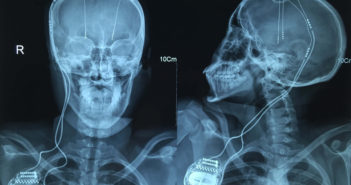

La estimulación cerebral profunda es considerada mundialmente como el tratamiento estándar para algunos pacientes con Parkinson.